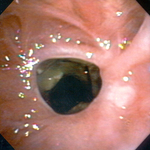

Bronchoscopic therapy for central airway obstruction of the right mainstem: post-mechanical debulking

From the collections of Jose Fernando Santacruz MD, FCCP, DAABIP and Erik Folch MD, MSc; used with permission